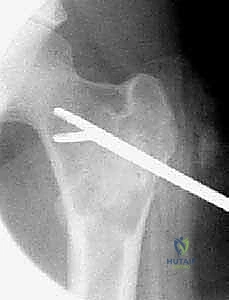

تُظهر هذه الأشعة السينية (X-ray) كيس عظم أحادي الغرفة (UBC) في الجزء العلوي من عظم العضد. لاحظ كيف أن الكيس يسبب ترققاً في قشرة العظم دون أن يخترقها.

- في الـ UBC، تظهر الآفة كمنطقة شفافة (سوداء) مركزية داخل العظم. وهناك علامة مميزة تُسمى "علامة الورقة المتساقطة" (Fallen Leaf Sign)، حيث تسقط قطعة صغيرة من قشرة العظم المكسورة داخل الكيس المملوء بالسائل، وهي علامة مؤكدة بنسبة 100% تقريباً على الـ UBC.